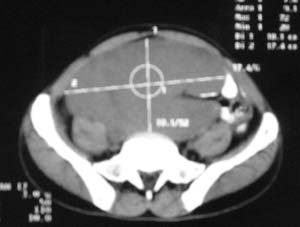

以下是引用zjzjr在2007-9-27 22:20:00的发言:[br]肠腔受推移,未见明显扩张及液平,所以考虑是肠外病灶, 间叶源性肿瘤?脂肪瘤?建议增强。

以下是引用guzhongliangddd在2007-9-27 23:21:00的发言:[br][br]与肠内高密度相同,病灶应该没有钙化,我认为首先考虑是间叶组织的良性肿瘤。建议楼主做后重建观察。中线区域大血管旁未见确切增大淋巴结。病灶对肠道只是推移关系。

以下是引用余辉在2007-9-27 22:24:00的发言:[br]暂考虑肠道间质来源肿瘤如小肠平滑肌肉瘤/瘤可能,应该增强